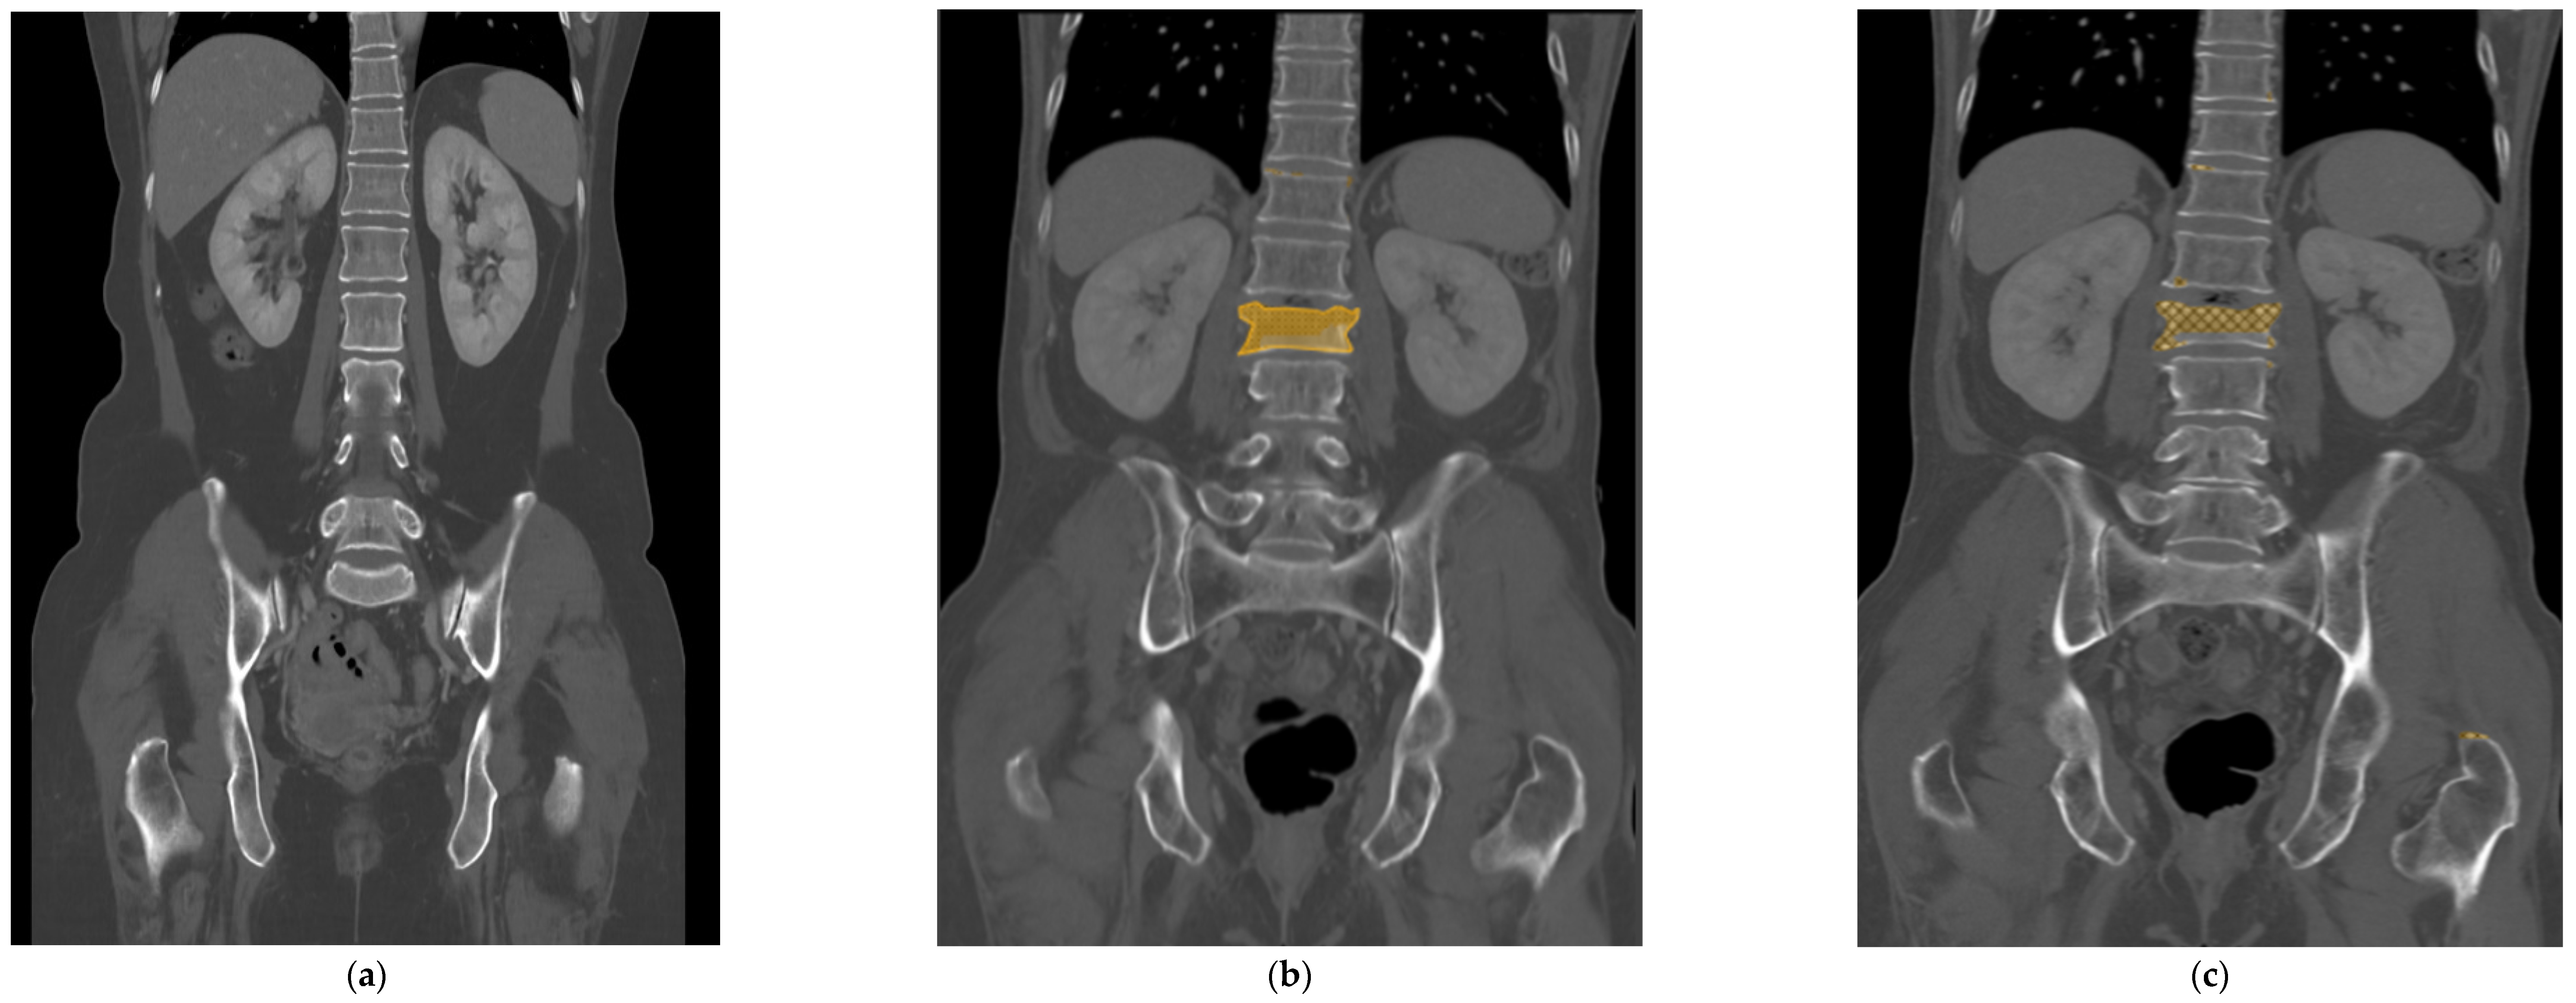

All the selected images were resized to 512 × 512 pixels and uploaded to Neuro-T, version 3.0.0 architecture (Neurocle Inc., Seoul, Republic of Korea). Then, as shown in Figure 2, any visibly fractured vertebral bodies in each image were labeled manually with a colored polygon along the outer margin of the cortex, including as many bone fragments as possible identified by one radiologist (reader 2). The dataset was randomly divided into 85% training and 15% test datasets for model development and accuracy predictions. The primary outcomes of the model were the test accuracy, precision, and F1 score. After training the model using the images, the predicted score of predicted fractured areas was calculated, ranging from 50 to 100%, and displayed as boxes and pixels on the image, like in Figure 2 and Figure 3. The predicted scores then were evenly classified into four groups (no score, normal; from 50 to 66.67%, indeterminate; from 66.68 to 83.33%, probable fracture; above 83.34%, fracture).

Figure 2.

The selected input image was resized to 512 × 512 pixels (a). Using the Neuro-T software, version 3.0.0 architecture (Nerocle Inc., Seoul, Republic of Korea), a yellow-colored polygonal box was drawn manually along the outer margin of the cortex, which had the fracture confirmed on a recent MRI, including as many bone fragments as possible (b). After the deep learning process was trained on these features, the predicted fractured areas, for which predicted scores ranged from 50 to 100%, were shown on the image with a checked pattern in pixels (c). This case was evaluated as a true positive result.